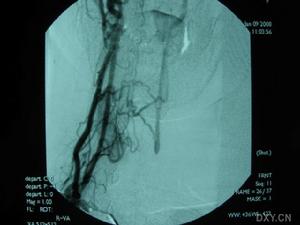

2.數字減影血管造影(DSA)重點觀察主動脈弓兩側鎖骨下動脈及頸總動脈等血管。若發現鎖骨下或頭臂幹上,椎動脈起始部的近心段有嚴重狹窄(多為管腔的85%)或幾乎閉塞,甚至同時可見造影劑經對側椎動脈上行至基底動脈又下行(逆流)至患側鎖骨下動脈的遠心段更可確診。

主動脈縮窄SSS確診主要靠腦血管造影,為避免血管造影時引起椎動脈起始段功能性狹窄,有條件的地方,最好行全腦血管造影以明確診斷。經股動脈穿刺腦血管及患側上肢血管造影可明確閉塞部位,有利於外科手術治療。對於急性鎖骨下動脈閉塞者,最好於閉塞後3天內行取栓術,有利於血液再通,避免再次栓塞。本組1例取栓術後至今已4年,配合抗凝治療,未再出現缺血症狀。大多數作者對SSS手術治療有較好的評價,鎖骨下與頸總動脈架橋術,是治療本症最常用的方法。對於少數長期狹窄的SSS患者且無急性腦損害者,尤其是壯年患者,可試用抗血小板聚集劑(6個月或以上)以及病因治療觀察。經顱多普超聲(TCD)可以連續及動態觀察椎動脈、基底動脈血流方向和速度,觀察顱內其他動脈被盜血的影響程度,是盜血綜合徵的敏感指標,可以評價治療效果和隨診。